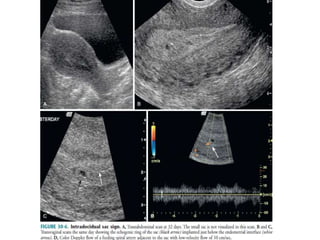

INTRADECIDUAL SAC SIGN:

 First reliable gray scale evidence of an IUP is

visualization of the gestational sac within the

thickened decidua ( echogenic focal area at the site of

implantation).

 An intradecidual gestational sac should be

eccentrically located within the endometrium and

should abut the endometrial canal.

 It is important to ensure that the sac abuts the

endometrial canal to distinguish an intra-uterine

gestational sac from a decidual cyst.